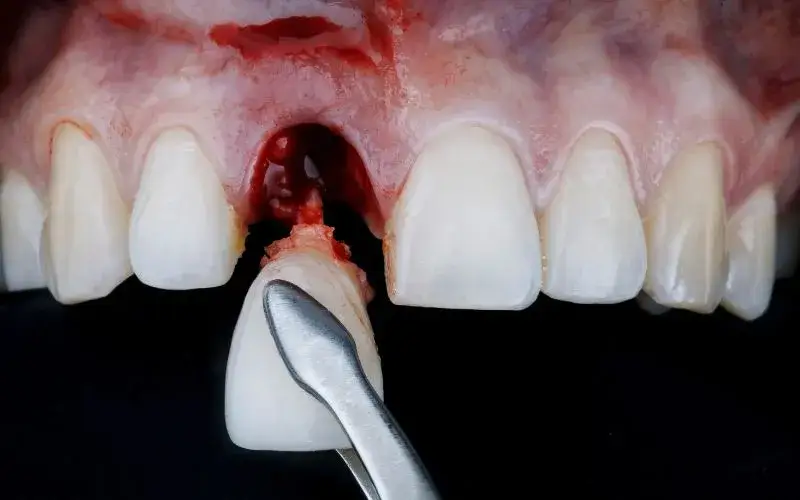

Dlaczego rana po ekstrakcji musi krwawić? Kluczowa rola skrzepu

Zapewne zastanawiasz się, dlaczego po wyrwaniu zęba rana musi krwawić. Otóż krwawienie z zębodołu po ekstrakcji jest całkowicie naturalnym i niezbędnym elementem procesu gojenia. To właśnie krew, która wypływa z rany, tworzy skrzep w zębodole. Ten skrzep jest niczym naturalny opatrunek, który chroni ranę przed infekcjami i stanowi fundament dla regeneracji tkanek. Bez niego proces gojenia byłby znacznie utrudniony, a ryzyko powikłań znacznie wyższe. Dlatego tak ważne jest, aby pozwolić mu się uformować i przede wszystkim go chronić.

Pierwsze minuty i godziny: jak długo powinno trwać intensywne krwawienie?

Bezpośrednio po zabiegu ekstrakcji zęba krwawienie jest najbardziej intensywne. Z mojego doświadczenia wynika, że najsilniejsze krwawienie utrzymuje się zazwyczaj przez pierwsze 30-60 minut. To właśnie w tym czasie formuje się stabilny skrzep. Stopniowo, w ciągu kilku godzin, krwawienie powinno znacznie się zmniejszyć lub całkowicie ustać. Jeśli jednak masz wrażenie, że krwawienie jest zbyt obfite lub nie ustępuje, warto zachować czujność i postępować zgodnie z zaleceniami, o których opowiem za chwilę.